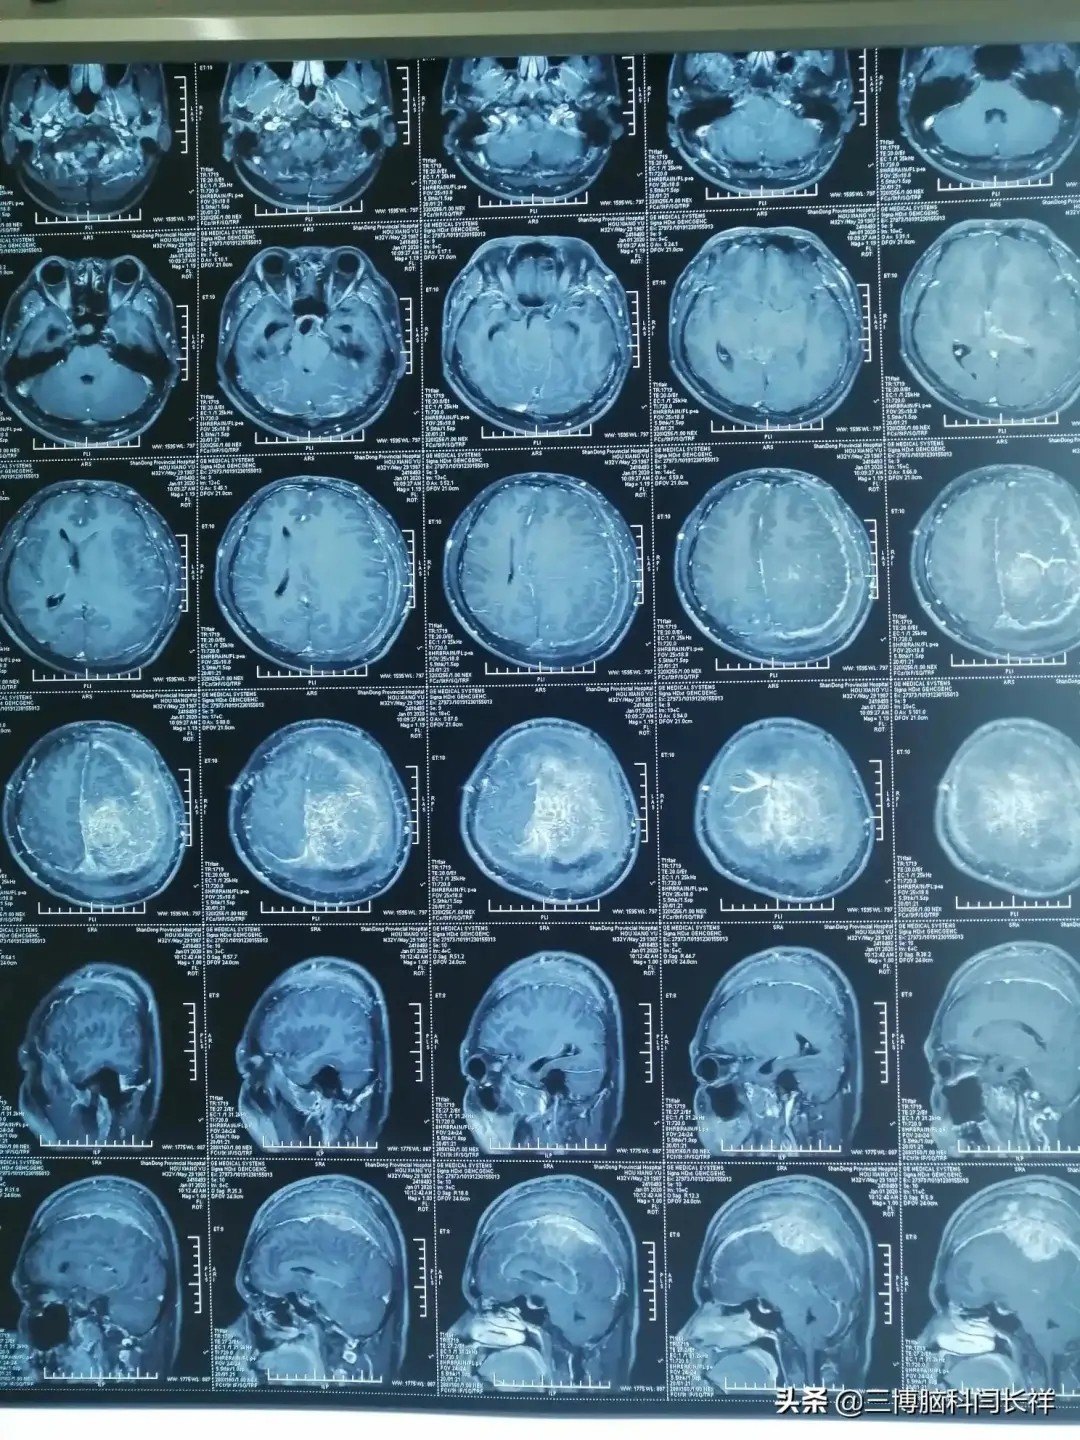

图片尺寸3968x2976

一例老年脑瘤病人术后现在恢复良好